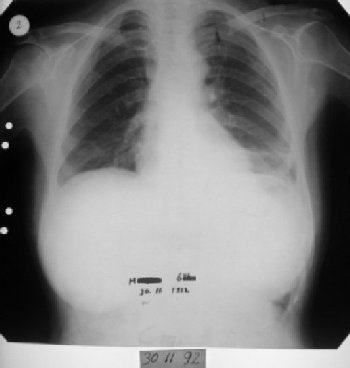

53 yaşında kadın hasta • 9 ayda tam iyileşme

1991 yılında az diferansiye fibröz malign mezotelioma teşhisi konulan 53 yaşındaki kadın hasta, çok düşkün haldeyken immünomodülatör tedavi ile 9 ayda tam iyileşme sağladı. 2000 yılında hasta remisyondaydı ve 9 yıl boyunca hastalık belirtisi göstermedi.

1991 Eylül - İlk Başvuru

Nefes darlığı, göğüs ağrısı - plevral sıvı

Aralık 1991 - Tedavi Başlangıcı

Çok düşkün hal, ödem, haftada 6 gün 4 mg

1991 Eylül: 53 yaşındaki kadın hasta nefes darlığı ve göğüs ağrısıyla başvurdu.

Tetkiklerde sol plevra boşluğunda sıvı saptandı.

Torakoskopi ve Coparvacs uygulamasına rağmen akciğerde tam ekspansiyon sağlanamadı.

11 Aralık 1991: Hasta uzman hekime getirildi.

Çok düşkün haldeydi, ödem ve kilo kaybı vardı.

Hasta terminal evredeydi ve acil müdahale gerekiyordu.